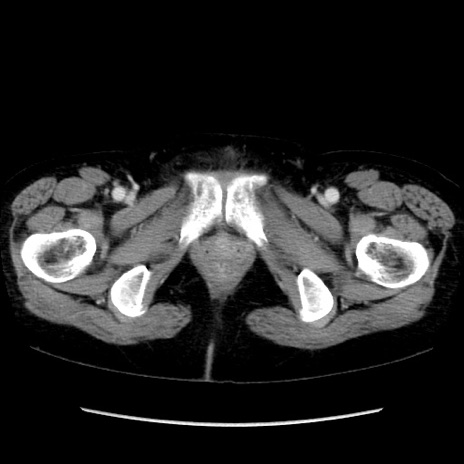

症例32(横断像)

【症例】40歳代 女性

【主訴】上腹部痛、嘔気・嘔吐

【現病歴】約9時間前頃から急に上腹部痛、嘔気、嘔吐が出現。改善しないため救急要請。

【既往歴】子宮頚癌(広汎子宮全摘術、放射線療法)、腸閉塞

【身体所見】腹部:平坦、軟、腸雑音亢進、上腹部を中心に腹部全体に圧痛あり。

【データ】WBC 8400、CRP 0.03